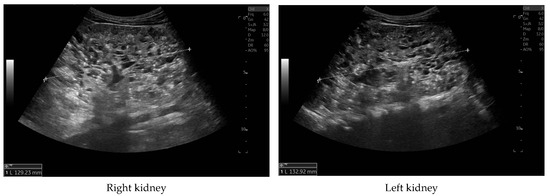

Currently, the boy is 5 years old. The US is similar to the previous one: elevated kidneys length (right: 130 mm (z-score 6.19); left: 133 mm (z-score 6.50)), with increased echogenicity, blurred corticomedullary differentiation, and multiple cysts with a maximum diameter up to 13–15 mm. The liver has a normal size, with numerous cysts up to 16 mm in diameter, with the largest cluster of cysts measuring 43 × 23 × 31 mm (Figure 3 and Figure 4). Laboratory tests show increased creatinine 0.79 mg/dL, urea 69,6 mg/dL, cystatin C 1.71 mg/L, uric acid 6.9 mg/dL, urine albumin to creatine ratio (ACR) 118.6 mg/g, and decreased GFR 55 mL/min/1.73 m2—stage III CKD. Other tests, including electrolytes, liver function, and urinalysis, were normal. The boy demands antihypertensive multi-drug therapy: angiotensin-converting enzyme inhibitors (ACEIs), calcium channel blockers, and beta-blockers.

Figure 3. Ultrasonography of kidneys at the age of five years.